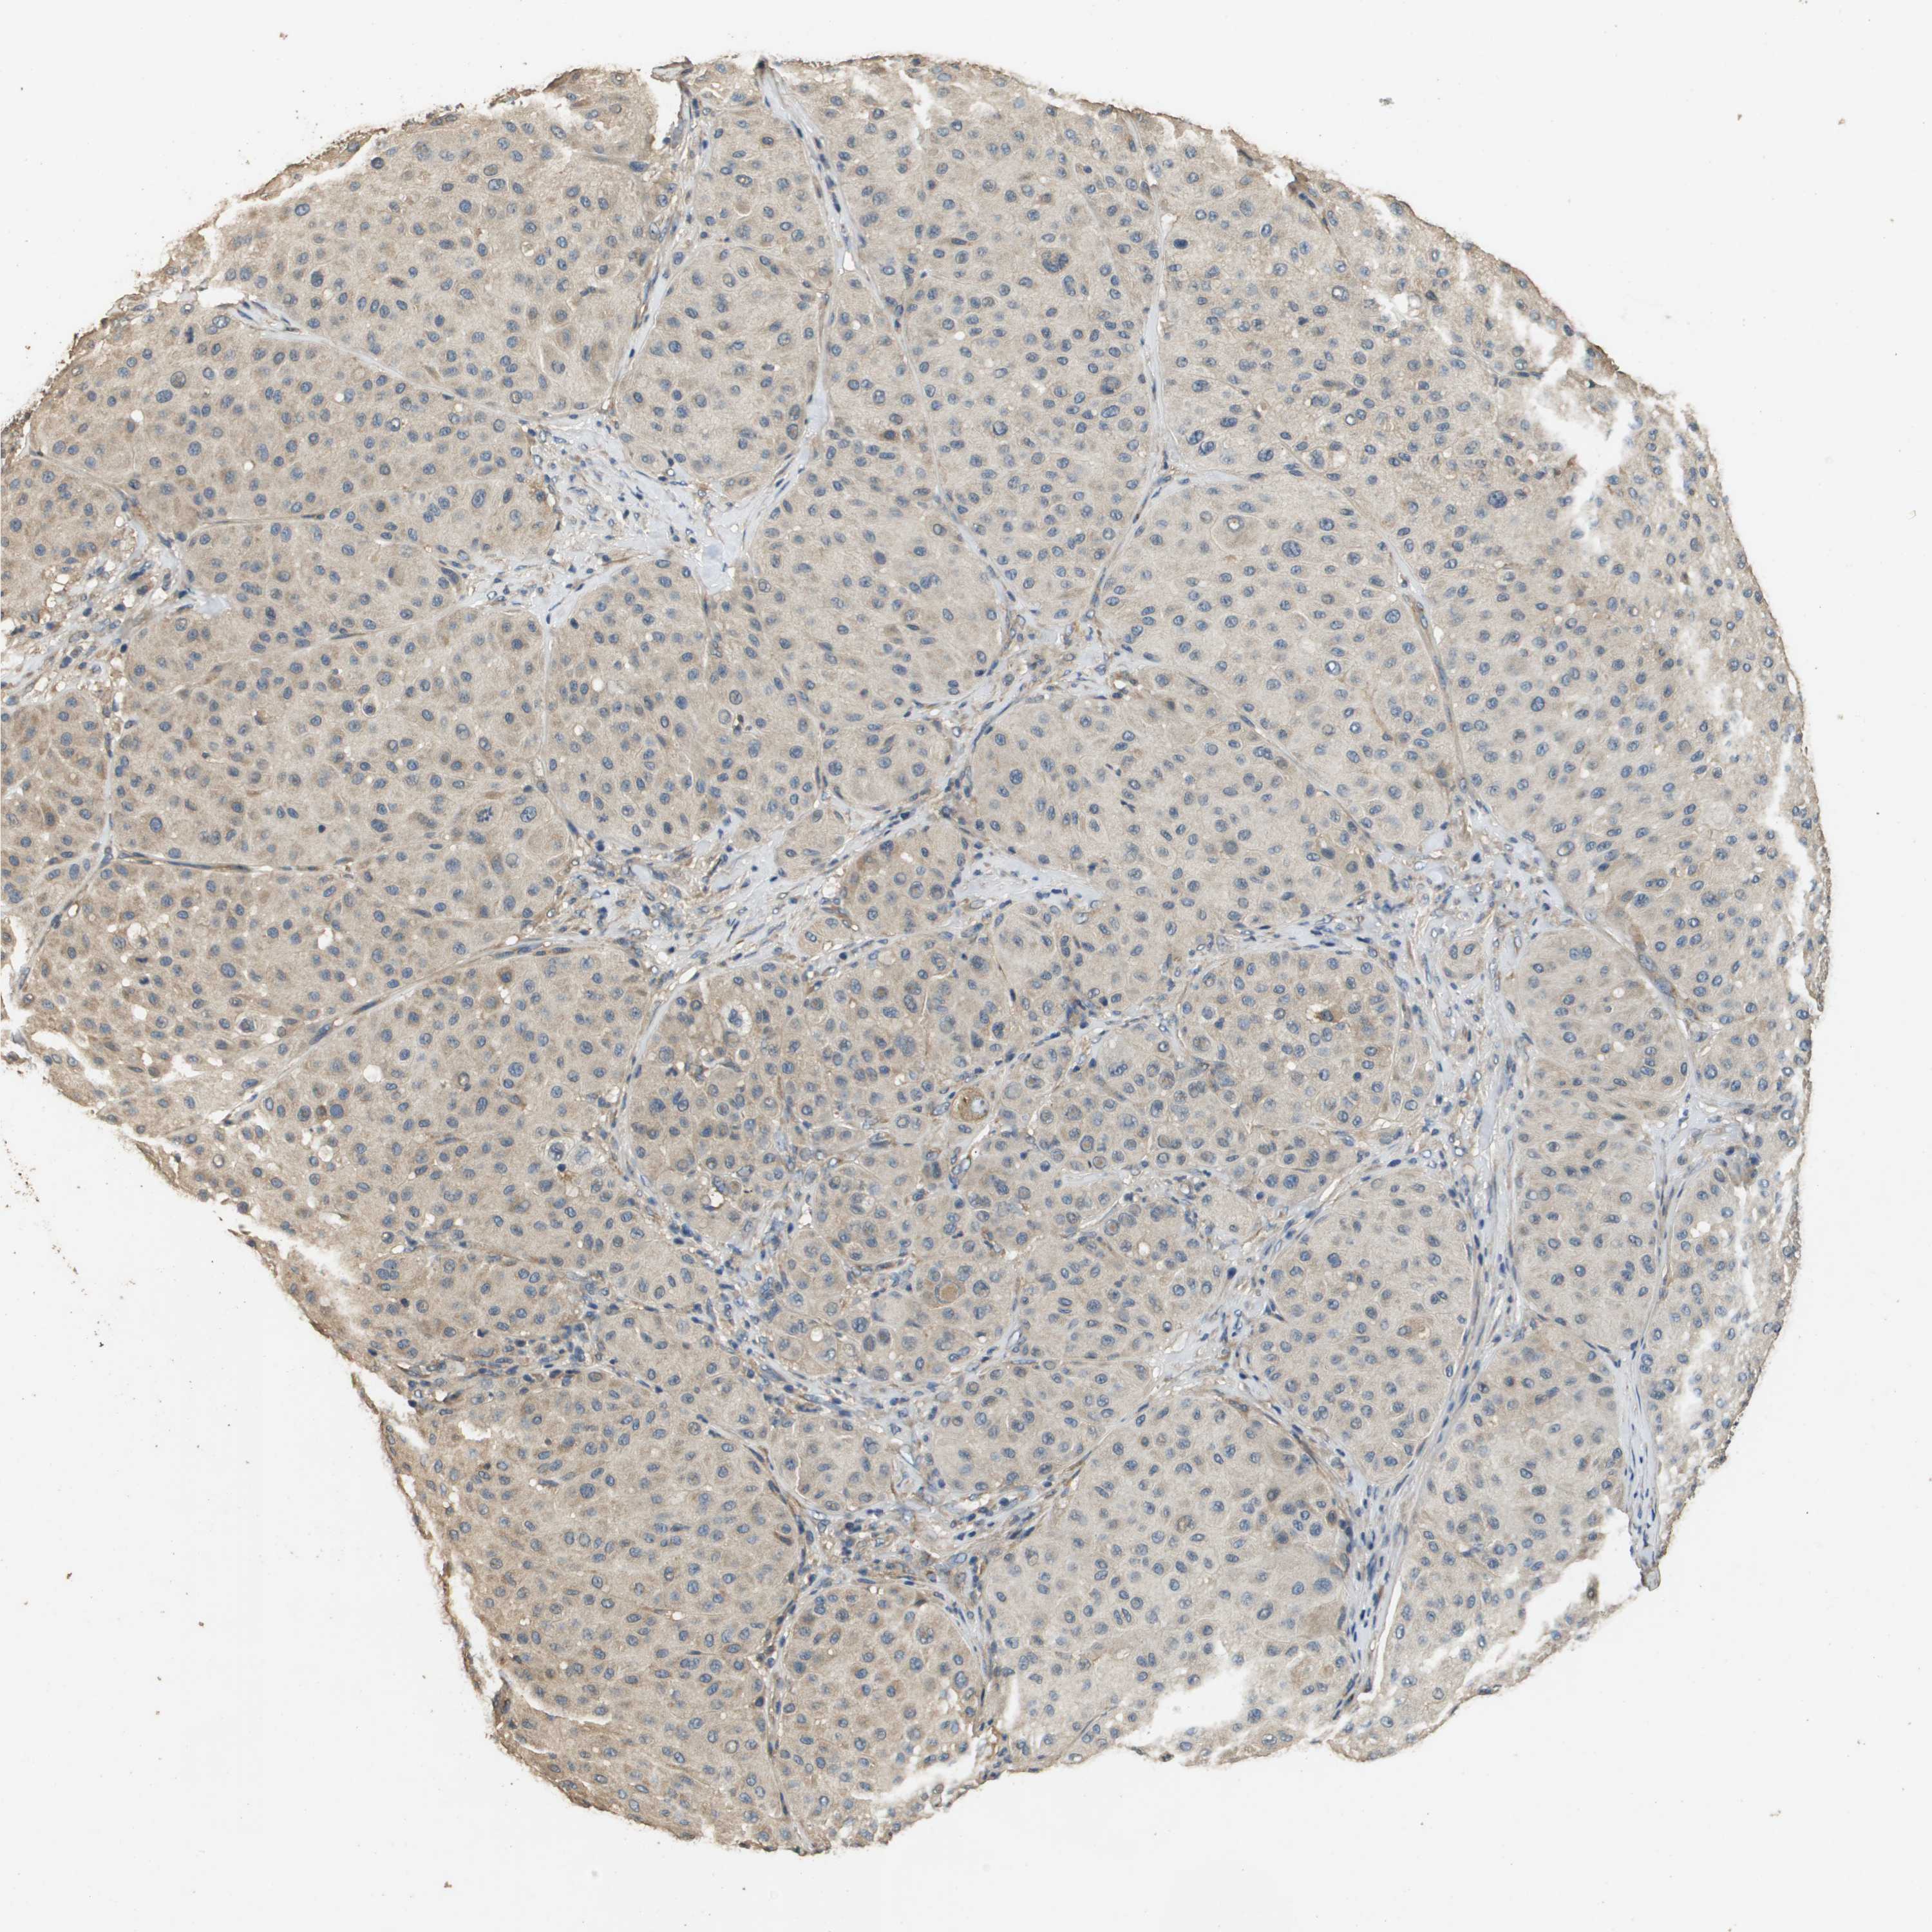

MELANOMA - Protein expressioni

A mouse-over function shows sample information and annotation data. Click on an image to view it in a full screen mode. Samples can be filtered based on level of antibody staining by selecting one or several of the following categories: high, medium, low and not detected. The assay and annotation is described here.

Note that samples used for immunohistochemistry by the Human Protein Atlas do not correspond to samples in the TCGA dataset.

Antibody stainingi

Antibody staining in the annotated cell types in the current human tissue is reported as not detected, low, medium, or high, based on conventional immunohistochemistry profiling in selected tissues. This score is based on the combination of the staining intensity and fraction of stained cells.

Each image is clickable and will lead to virtual microscopy that enables deeper exploration of all samples and also displays staining intensity scores, fraction scores and subcellular localization as well as patient and tissue information for each sample.

Antibody HPA059131

Antibody CAB017713

Staining

High

Medium

Low

Not detected

Intensity

Strong

Moderate

Weak

Negative

Quantity

>75%

75%-25%

<25%

None

Location

Nuclear

Cytoplasmic/membranous

Cytoplasmic/membranous,nuclear

Malignant melanoma, NOS

Malignant melanoma, Metastatic site